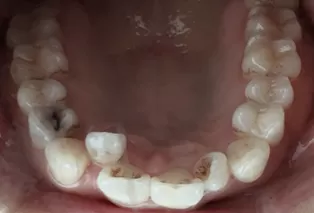

Photos intra-orales